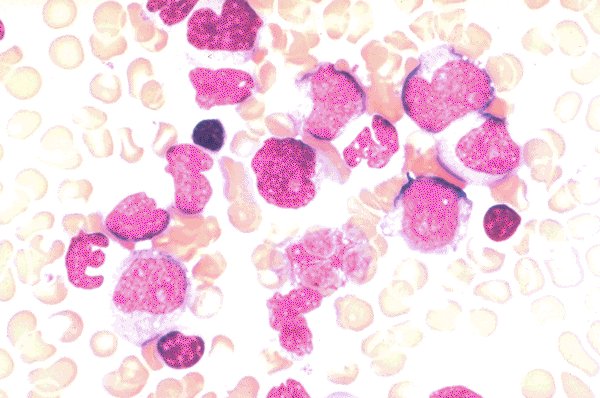

Slide 21B of 48 Image ID 2658

Myelodysplasia, Refractory Anemia with excess

blasts in transition (RAEBT)

Refractory Anemia with excess blasts in

transition (RAEBT). Several blasts with nucleoli as

well as abnormal red cells and granulocytes are

seen in this field.